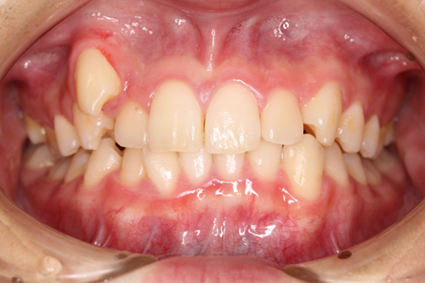

「矯正」と聞くと、多くの方が「表側矯正(唇側矯正)」を思い浮かべるのではないでしょうか。表側矯正では、矯正装置を歯の表側(唇側)に装着します。治療中に装置を取り外すことはできません。これにより、確実に歯を矯正することができます。

従来の表側矯正では、金属製のワイヤーや装置が目立ってしまうことがありました。口を開けると、矯正装置がはっきりと見えるため、見た目を気にされる方も少なくありません。しかし、最近では白いパーツを用いた装置が登場し、従来の金属製の装置に比べて目立たないよう工夫されています。このような改良により、審美性を保ちながら治療を進めることが可能です。

表側矯正は、他の矯正方法と比較して費用が比較的安価であることも大きな魅力です。予算に制限がある場合でも、手軽に始められる治療法として人気があります。また、軽度から重度の歯並びまで、幅広い症例に対応できるのも特徴の一つです。

また、当院では表側矯正ではなく、装置を歯の裏側に装着する「裏側矯正(舌側矯正)」も可能です。表側矯正よりもさらに審美性の高い治療が可能です。ご興味のある方はぜひご相談ください。